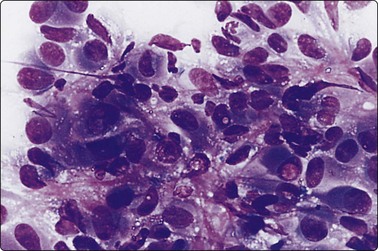

image image image

Fig. 6.28 Poorly differentiated carcinoma

(A,B) Smears showing syncytial clusters of crowded small cells with hyperchromatic nuclei (A, MGG, HP; B, Pap, HP); (C) Tissue section, same case. (H&E, IP).

Until recently, thyroid carcinoma with a poorly differentiated insular pattern was considered to be a distinct entity, a thyroglobulin-producing neoplasm, intermediate in aggressiveness between well-differentiated and anaplastic thyroid carcinoma. Reports have appeared documenting cytological features in insular carcinomas such as high cellularity, dispersed and loosely aggregated cells, solid, cohesive trabecular or papillaroid structures, intact insulae, fragile, ill-defined, granular cytoplasm, oval, hyperchromatic nuclei, occasional INCIs and/or grooves.151-155 However, as insular pattern is often admixed with trabecular and solid growth patterns, the more suitable term ‘primordial carcinoma’ was suggested for this entity.156

The current concept of pure poorly differentiated thyroid carcinoma, as per the Turin proposal156 is one that shows a histologically mixed solid/trabecular/insular architecture, absence of conventional nuclear features of PC and the presence of one of the following three features: cells with convoluted (raisin-like) nuclei, a mitotic index of ≥3 mitoses/10 high-power fields and tumor necrosis. Most tumors are immunohistochemically positive for thyroglobulin and thyroid transcription factor 1, and a subset is also positive for p53.157 Ras mutations are common.

Smears in poorly differentiated thyroid carcinomas are hypercellular with single cells as well as cells in solid, trabecular and insular patterns. There is marked crowding of cells and tumor cells show high nuclear cytoplasmic ratios (Fig. 6.28).158